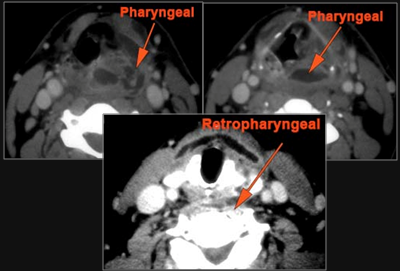

52-year old male with fever, dysphagia and possible aggressive pharyngitis or other infrahyoid neck infections involving the infra hyoid deep neck.Exam

There is edema/abscess or likely suppurative retropharyngeal adenitis involving the nasopharynx or adjacent deep tissue spaces. |

There is edema/abscess tonsillar or otherwise or likely suppurative retropharyngeal adenitis involving the oropharynx or adjacent deep tissue spaces. |

There is edema/abscess arising from the hypopharynx, larynx, thyroid gland or trachea. |

There is edema/abscess within the adjacent deep neck, and/or retropharyngeal space. |